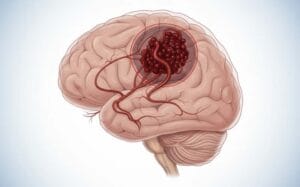

İnsan beyni karmaşık bir damar ağına sahiptir. Normal şartlarda atardamarlar kanı kılcal damarlara iletir. Fakat DAVF durumunda kan doğrudan toplardamara geçer. Bu durum damarlar arasında anormal bir bağlantıdır. Özellikle bu hatalı yol toplardamar basıncını hızla artırır. Sonuç olarak beyin dokusunda ciddi ödem gelişir. Ayrıca damar çatlaması riski her an mevcuttur.

Hastalık genellikle beyni saran dura zarında oluşur. Bu zar beynin en önemli koruyucu katmanıdır. Nitekim buradaki damarlar yüksek basınca uyum sağlayamaz. Dolayısıyla kan akış yönü tersine dönmeye başlar. Öte yandan bu durum doğuştan gelen bir bozukluk değildir. Genellikle yaşamın ilerleyen evrelerinde kendiliğinden ortaya çıkar. Beyin damar yapısındaki değişimler bu süreci tetikler. Uzman cerrahımız her hastada damar yapısını titizlikle inceler.

Fistül oluşumu beynin kan tahliye mekanizmasını bozar. Kan beyin dokusundan dışarıya verimli şekilde atılamaz. Sonuç olarak kafatası içi basınç tehlikeli şekilde yükselir. Bu durum kalıcı sinir hasarlarına yol açar. Profesyonel bir tedavi planı bu hasarları engeller. Uzman ekibimiz damar yolunuzu yeniden düzenler.